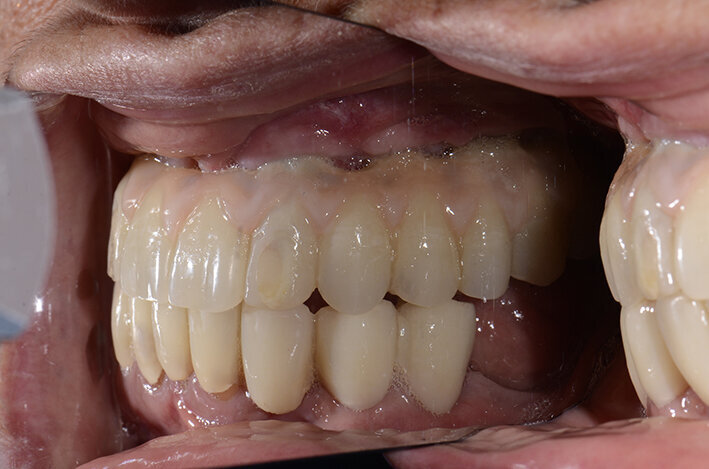

Procediamo quindi all’inserimento di sei impianti BLX Straumann (Straumann Group) (Fig. 43, 44), ed utilizziamo gli impianti posizionati nella tuberosità per stabilizzare la dima chirurgica e il provvisorio sul modello master di lavoro digitale. La funzionalizzazione del provvisorio immediato subito dopo l’intervento viene effettuata con l’utilizzo della tecnica DIL19 (Figg. 45, 46).

Il provvisorio immediato così funzionalizzato creerà un condizionamento ideale dei tessuti (Figg. 47-49) che porterà alla realizzazione del lavoro definitivo con la serenità di aver creato le condizioni per un successo a lungo termine del trattamento. L’immagine dei tessuti a tre mesi dal posizionamento implantare evidenzia i buoni auspici per un mantenimento a lungo termine degli impianti (Fig. 50).